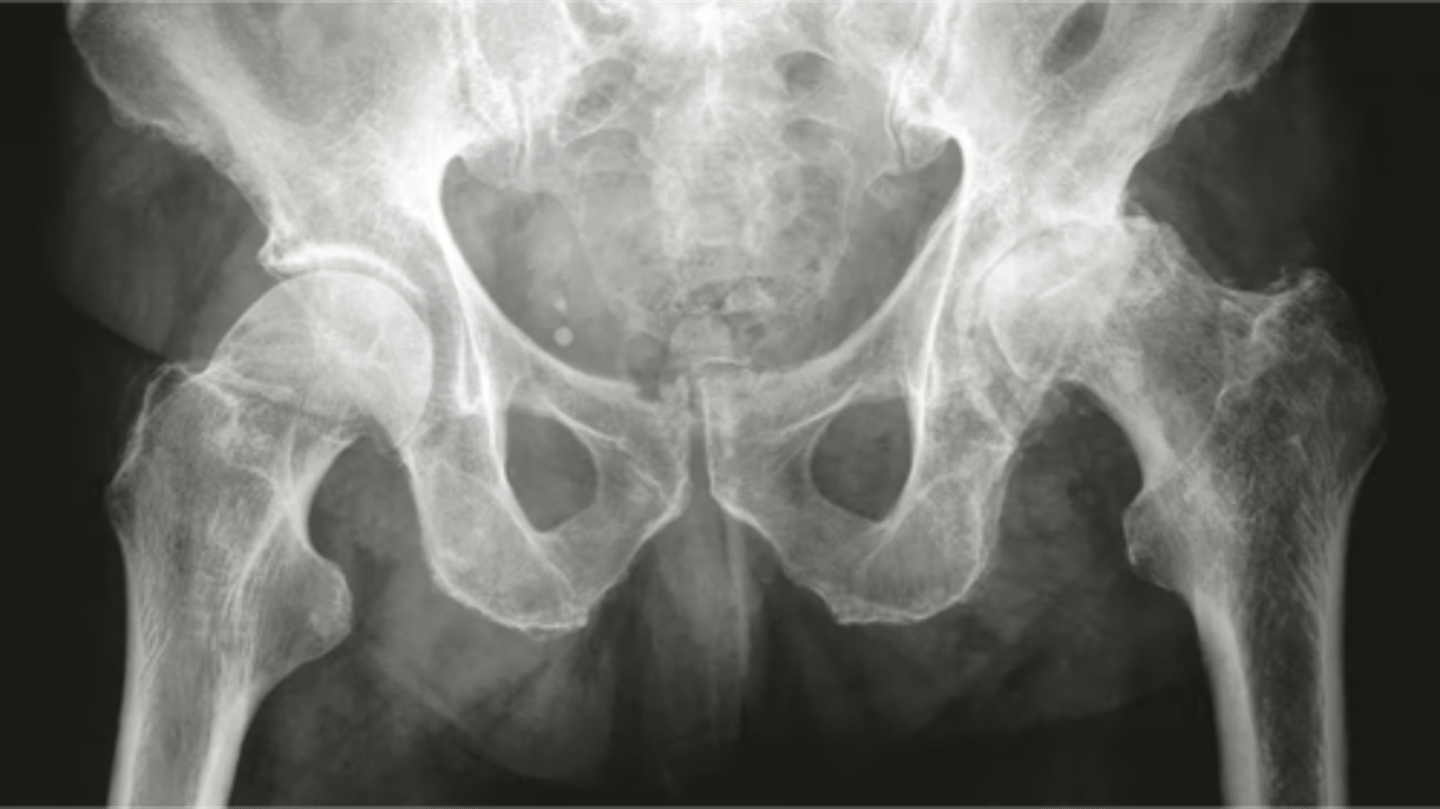

what does this x-ray show

osteoarthritis

radiograph "LOSS"

a. Loss of joint space

b. Osteophytes - spurs of bone

c. Subarticular sclerosis

Increased density of bone on joint line

d. Subchondral cysts

Small fluid filled holes in bone on the joint line

what is this

OA on left hip